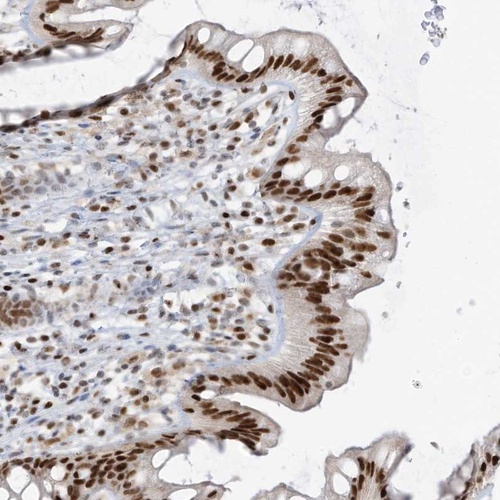

Immunohistochemical staining of human rectum shows strong nuclear positivity in glandular cells.